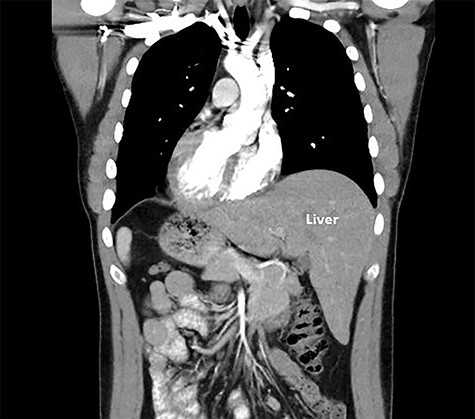

A 29-year-old male was referred for consideration of surgery in the setting of a CDH1 gene mutation. After thorough counseling and after observing the reassuring outcomes of his own family members that had undergone this surgery for the same genetic mutation, he elected to undergo a laparoscopic total gastrectomy and he elected to undergo a laparoscopic total gastrectomy. A computed tomography (CT) scan was undertaken for operative planning and demonstrated mirror-image anatomy, a characteristic of SIT (Fig. 1).

SIT is commonly associated with vascular aberrations, and previous relevant surgical cases have strongly recommended pre-operative anatomical arterial mapping [5]. We sought a CT angiography pre-operatively to ascertain the anatomy and detect any abnormal vascular structures that may complicate or confuse the surgery. Aside from the complete transposition of vascular structures to the opposite side, there was no additional variation to the branching pattern in the abdomen (Fig. 3).